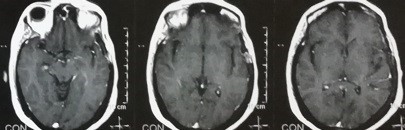

ورم سحائي بقاع الجمجمةبالفص الصدغي الايسر

left temporal lobe meningioma

Brain magnetic resonance imaging, cross-sections of a 56-year-old woman suffering from visual impairment and severe headaches. As shown in the pictures in the upper row, the tumor is located in the left temporal lobe, pressing on the carotid artery and the optic nerve on the left side. And the bottom row is the x-ray view of the same patient four months after successful surgery to remove the tumor without any complications.